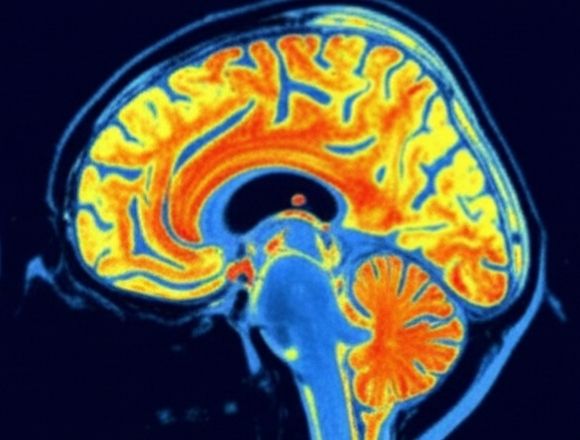

So ändert sich die Gehirnleistung nach 12 Wochen

Aufnahmen aus dem Testverlauf

*Basierend auf durchschnittlichen Ergebnissen von Studienteilnehmern